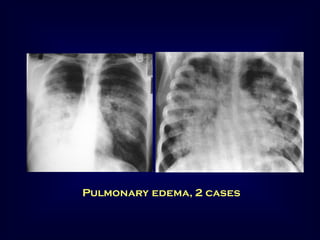

Pulmonary edema

Pulmonary edema, 2 cases

Diffuse pulmonary hemorrhage

Hemoptysis, anemia and air space opacities

Appear rapidly and clear within few days

Spare the lung apex and peripheral zones

Bilateral, may be asymmetric, air bronchogram

Repeated attacks → pulmonary fibrosis